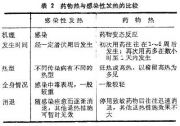

| 2021年7月26日 (一) 20:03 | 药物热与感染性发热的比较.jpg (文件) |  |

46 KB | Uploaded with SimpleBatchUpload | 3 |